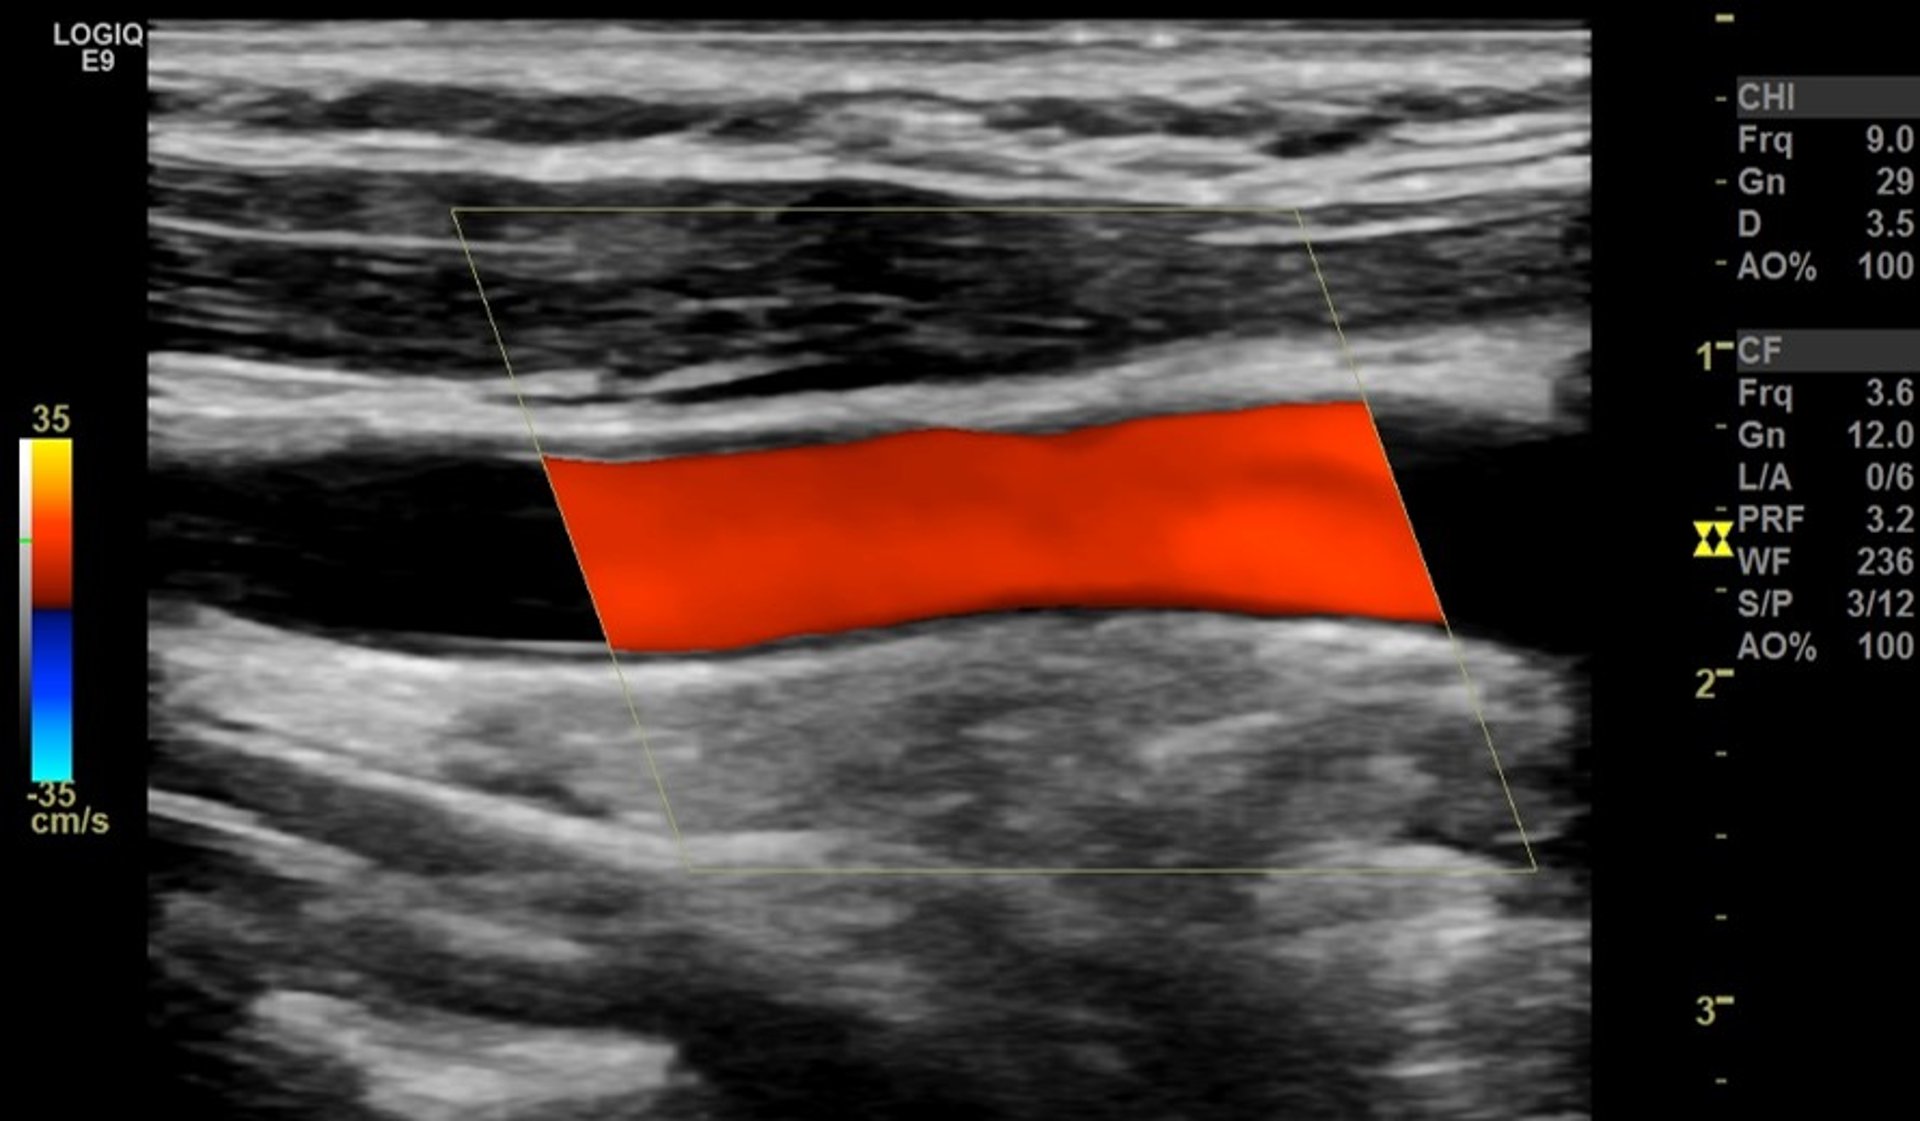

Farbkodierte Doppler-Sonografie der Halsschlagader (Carotis)

Der rote Streifen stellt den normalen, unbehinderten Blutfluss durch eine große Ader im Hals dar (Halsschlagader, Seitenansicht).

Aufnahme von Dr. med. Mustafa Mafraji (MD)